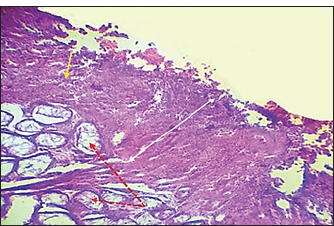

Fig. 7. Histopathological section of testes from a dog in the zinc gluconate group at 30 days post-intrasticular injection, showing exfoliation of germ cells (red arrows), infiltration of inflammatory cells (white arrows), Leydig cell clusters (yellow arrow), edema (star), and congestion (yellow head arrow) (H & E stain 10X). Surgical groupIn the surgical group (GII), the main characteristic findings at 30 days post-surgery were degeneration of seminiferous tubules, multinucleated spermatid, infiltration of inflammatory cells, atrophy of Leydig cells, and vacuole degeneration of basal and Sertoli epithelium (Fig. 8). Furthermore, there was loss of the straight shape of the tubuli recti, disequimentaion of the tubuli recti epithelium, and proliferation of myoid cells (Fig. 9). Other sections showed coagulative necrosis and ghost tubules in the rete testis (Figs. 10 and 11).

Fig. 8. Histopathological section of testes from dogs in the surgical group at 30 days post-surgery, showing degeneration of seminferous tubules (red dotted arrow), multinucleated spermatid (yellow arrows), infiltration of inflammatory cells (red arrow), atrophy of Leydig cells (black arrow), and vacuole degeneration of basel and sertoli epithelium (black dotted arrow) (H & E stain 10X).

Fig. 9. Histopathological section of testes from a dog in the surgical group at 30 days post-surgery, showing loss of the straight shape of the tubuli recti (yellow arrow), disequilibrium of the tubuli recti epithelium (black arrow), proliferation of myoid cells (red arrow), and infiltration of inflammatory cells (red dotted arrow) (H & E stain 40X).

Fig. 10. Histopathological section of testes from a dog in the surgical group at 30 days post-surgery, showing coagulative necrosis (red arrow), ghost tubules in the rete testis (red dotted arrow), and infiltration of inflammatory cells (red head arrow) (H & E stain 10X).

Fig. 11. Histopathological section of testes from a dog in the surgical group at 30 days post-surgery, showing tunica albuginea thickening (white arrows with two heads), inflammatory cell infiltration (yellow arrow), and vacuolar degeneration (red dotted arrow) (hematoxylin and eosin stain 4X). Control groupIn the control group, the histopathological testicular section expresses interstitial septa that surround the seminiferous tubules and contain Leydig cells. Various stages of spermatogenesis and Sertoli cells were also recognized (Fig. 12).